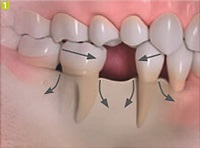

gyökere fogat rágás hordozza a terhelést az állkapocs csont, így megakadályozza rezorbtsiyu.Odnako ha a beteg elveszíti egy vagy több foga van, az állcsont nem kapja meg a szükséges stimuláció és kezd oldódni. Ennek eredményeként, a fogak mindkét oldalán fogatlan intervallumot eltolódott egymáshoz, ami a megjelenését a fogak közötti rések, mint alább látható.

Csontreszorpciót után egy ideig a fogak elvesztéséhez